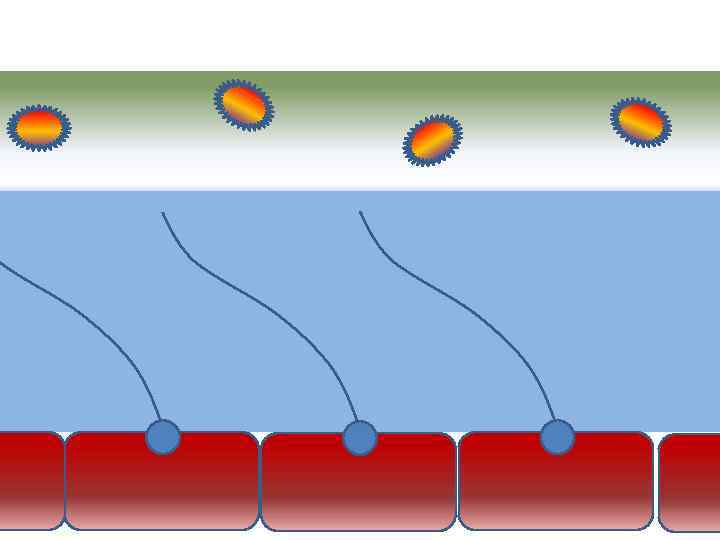

Факторы риска Недостаточное увлажнение дыхательной смеси Высушивание трахеи и бронхов

Факторы риска Недостаточное увлажнение дыхательной смеси Высушивание трахеи и бронхов

Факторы риска Недостаточное увлажнение дыхательной смеси ! Слизистая оболочка трахеи и бронхов обязательно должна быть укрыта секретом

Факторы риска Недостаточное увлажнение дыхательной смеси ! Слизистая оболочка трахеи и бронхов обязательно должна быть укрыта секретом

Факторы риска Недостаточное увлажнение дыхательной смеси • естественное удаление бактерий • состояние эпителия трахеи и бронхов

Факторы риска Недостаточное увлажнение дыхательной смеси • естественное удаление бактерий • состояние эпителия трахеи и бронхов

Оптимальное увлажнение 37°С, 44 мг/л Оптимальная влажность • Уменьшает время нахождения патогенной флоры в легком

Оптимальное увлажнение 37°С, 44 мг/л Оптимальная влажность • Уменьшает время нахождения патогенной флоры в легком

Движение клеток реснитчатого эпителия Движение вперед 1 – 3 Обратное движение 4 – 8

Движение клеток реснитчатого эпителия Движение вперед 1 – 3 Обратное движение 4 – 8

Оптимальное увлажнение Достаточная продукция слизи Хороший транспорт Экономит энергию и воду Защитная функция

Оптимальное увлажнение Достаточная продукция слизи Хороший транспорт Экономит энергию и воду Защитная функция

Механизм защиты легкого Слизь (зеленый цвет) нейтрализует и связывает патогенную флору(синий цвет) Слизь – это барьер между клетками и патогенной флорой Слизь – это транспортное средство

Механизм защиты легкого Слизь (зеленый цвет) нейтрализует и связывает патогенную флору(синий цвет) Слизь – это барьер между клетками и патогенной флорой Слизь – это транспортное средство

Нормальное состояние слизистого бронхиального секрета возможно только при 100% относительной влажности воздуха

Нормальное состояние слизистого бронхиального секрета возможно только при 100% относительной влажности воздуха